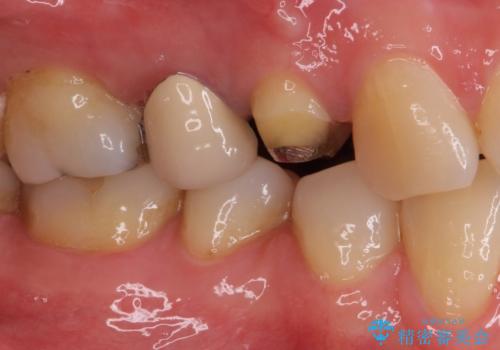

- クラウンが割れて治療を行っていたものの、途中で放置してしまったとのことで来院された患者様です。

根管治療を行った後に、ガラス系セラミッククラウンにて補綴することとしました。

透明感のある自然な仕上がりとなり、患者様には大変満足していただきました。